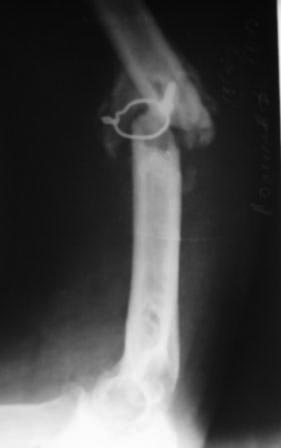

[Ortho] Ложный сустав плечевой кости

Пациент 1942г.р. 4 месяца назад оперирован в экстренном порядке в другом

областном неотложном центре, 20 дней назад гипс снят и направлен к нам.

Пациент активный, оптимист, никогда ничем не болел. Локально: тугой

ложный сустав с варусной деформацией, клиника полного повреждения

лучевого нерва (со слов, до операции также рука висела), контрактура

локтевого сустава, разгибательная контрактура л/з сустава и

пальцев,воспалительных изменений нет. От предложенного БИОС по

финансовым соображениям отказался.

Предварительный план лечения: удаление металлоконструкций,

ревизия лучевого нерва (возможно, пластика нерва), освежение концов до

появление "росы", и адаптация концов возможно по типу "русского замка",

фиксация либо аппаратом Илизарова, либо пластиной ( у нас обычные

пластины ЦИТО типа DCP), возможно укорочение на 2-3 см, но это

для плеча большого значения не имеет, главное - ранняя и усиленная